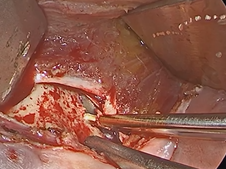

Transcervical Exploration of Parapharynx for Deep Lobe Parotid Pleomorphic Adenoma

- Date : 01/01/2020